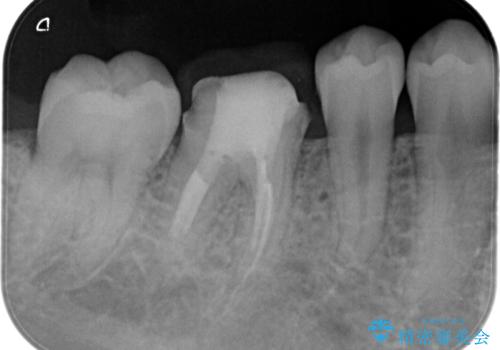

【根管治療】ラバーダムと顕微鏡を用いた治療

- 奥歯の治療の継続を主訴に来院された患者様です。

他院にて根管治療を行ったそうですが、ラバーダムを使用していなかったため、クラウン修復の前に当院の治療を希望され受診されました。

根管内に充填されている材料は、スカスカの状態で簡単に除去ができました。

術後1年経過を見ていますが、問題なく良好な経過をたどっています。